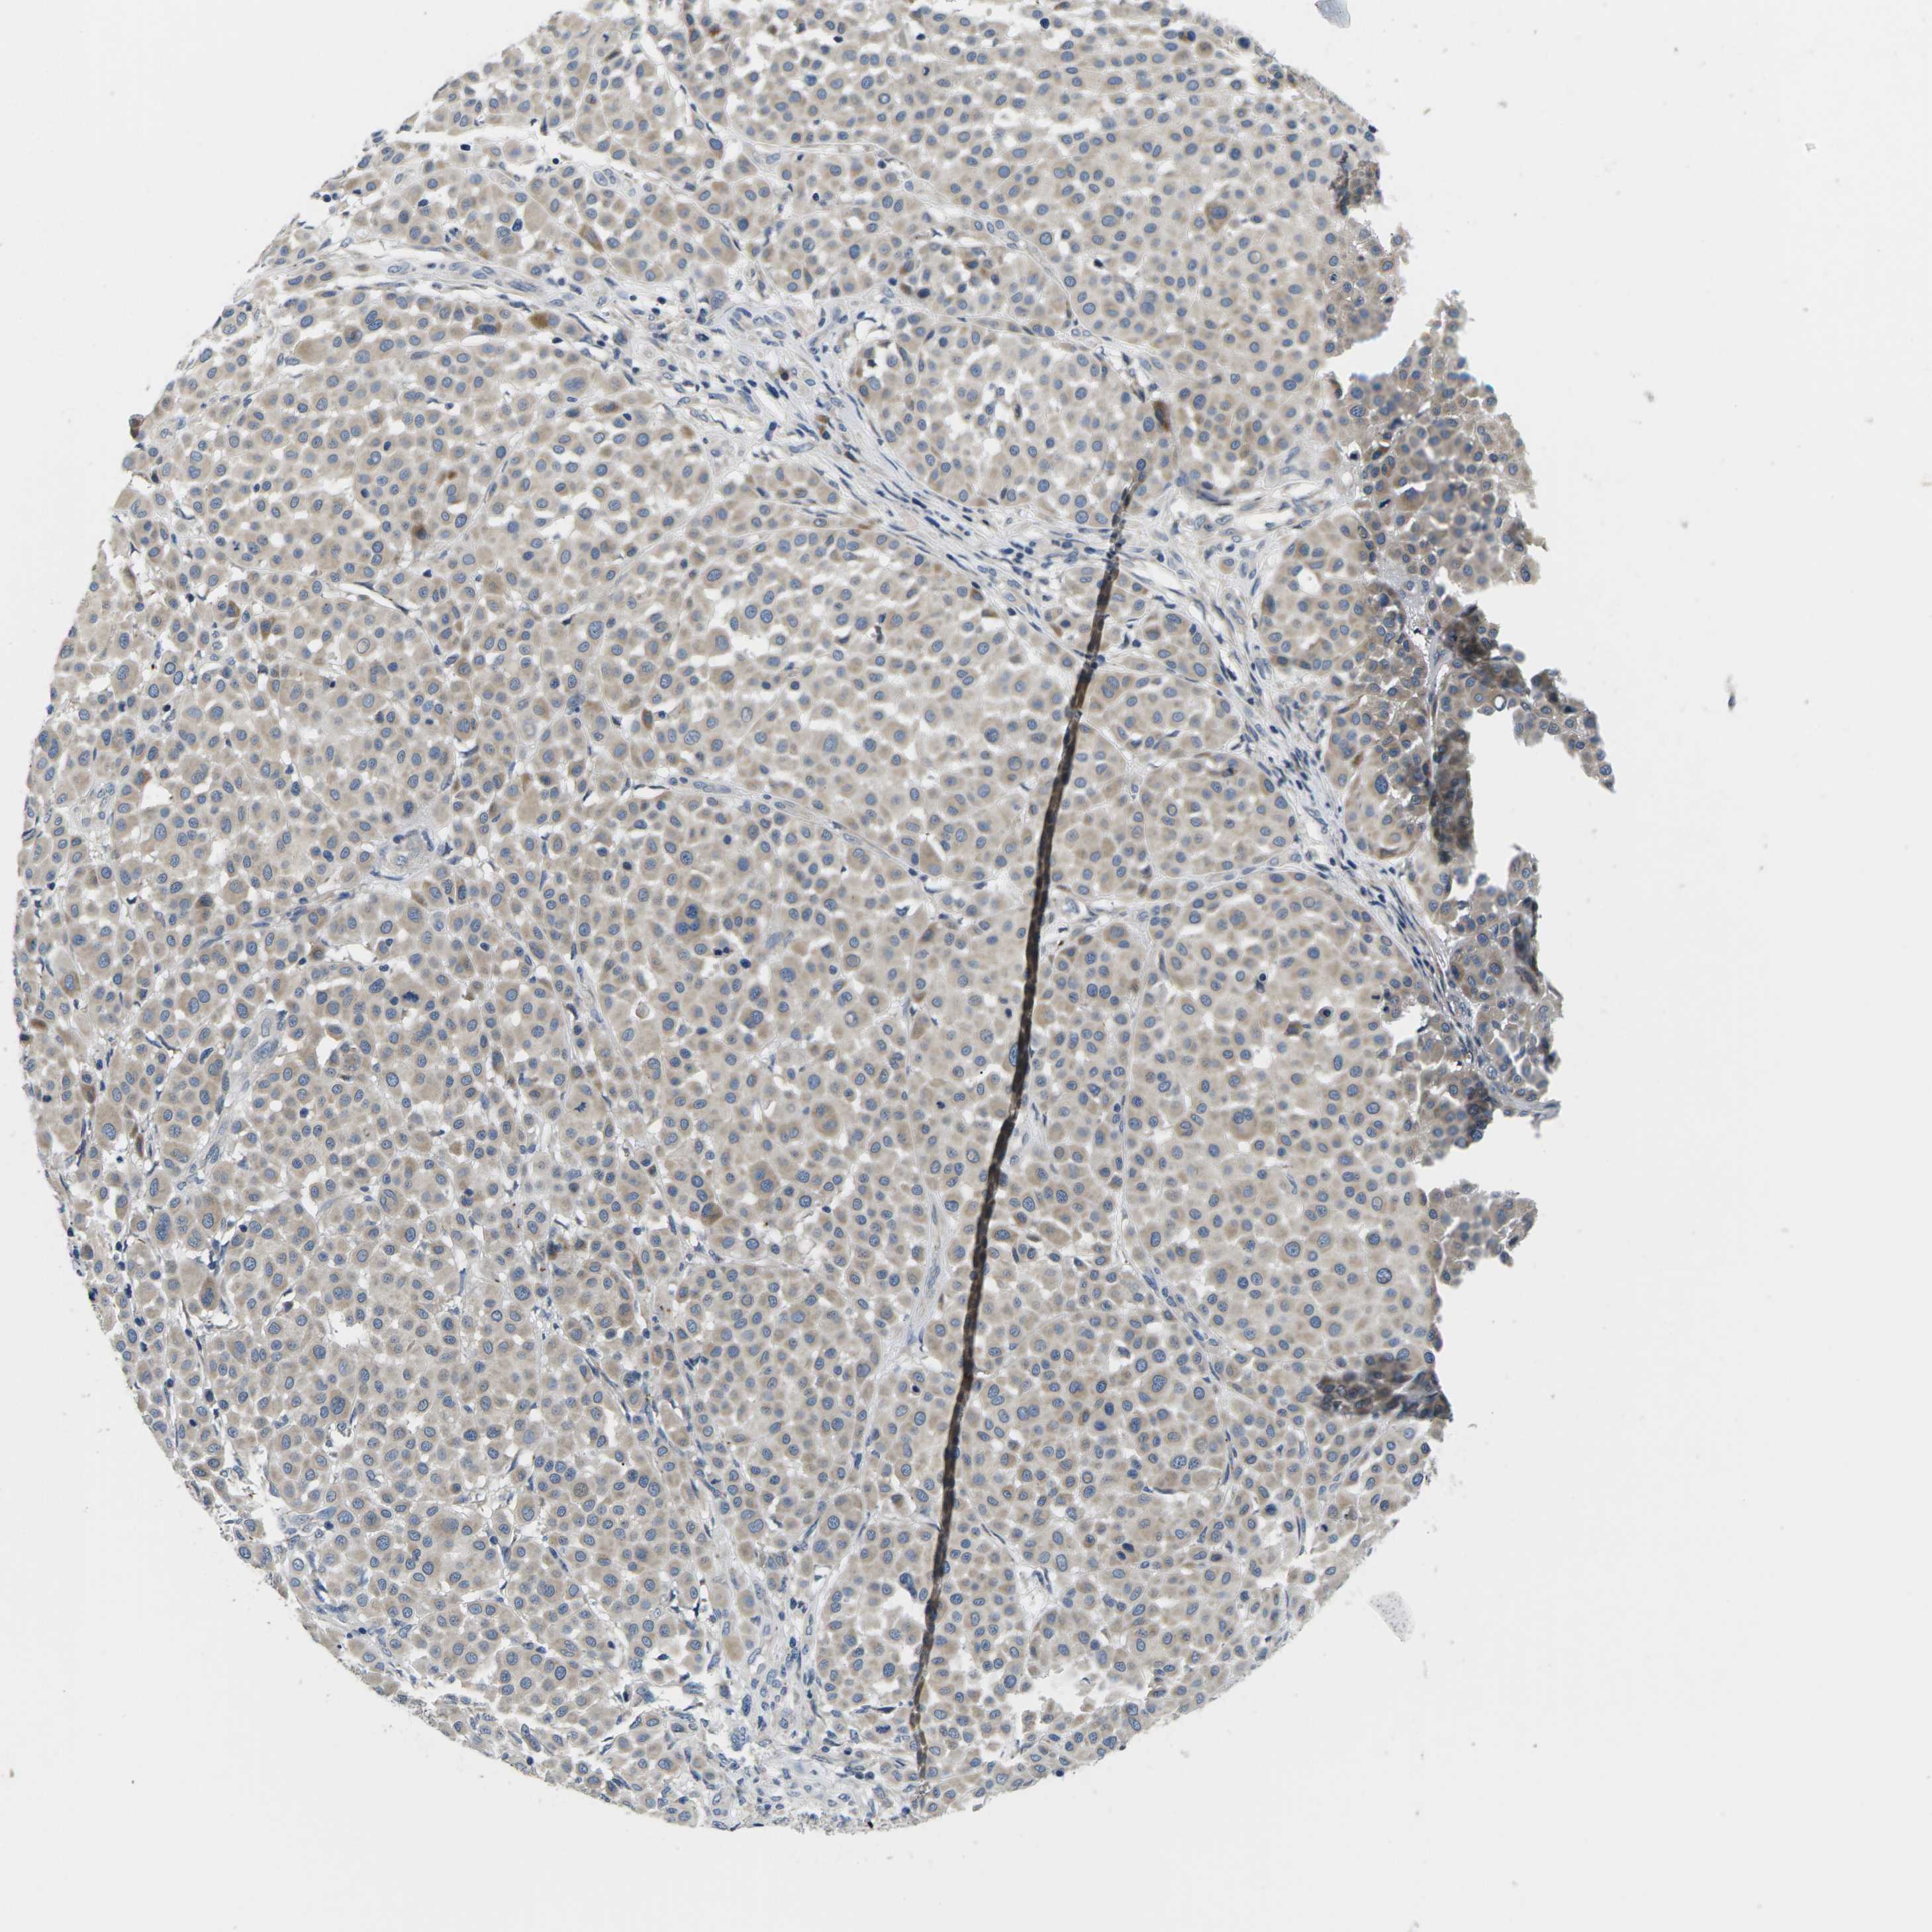

MELANOMA - Protein expressioni

A mouse-over function shows sample information and annotation data. Click on an image to view it in a full screen mode. Samples can be filtered based on level of antibody staining by selecting one or several of the following categories: high, medium, low and not detected. The assay and annotation is described here.

Note that samples used for immunohistochemistry by the Human Protein Atlas do not correspond to samples in the TCGA dataset.

Antibody stainingi

Antibody staining in the annotated cell types in the current human tissue is reported as not detected, low, medium, or high, based on conventional immunohistochemistry profiling in selected tissues. This score is based on the combination of the staining intensity and fraction of stained cells.

Each image is clickable and will lead to virtual microscopy that enables deeper exploration of all samples and also displays staining intensity scores, fraction scores and subcellular localization as well as patient and tissue information for each sample.

Antibody HPA015242

Antibody HPA015968

Staining

High

Medium

Low

Not detected

Intensity

Strong

Moderate

Weak

Negative

Quantity

>75%

75%-25%

<25%

None

Location

Nuclear

Cytoplasmic/membranous

Cytoplasmic/membranous,nuclear

Malignant melanoma, NOS

Malignant melanoma, Metastatic site